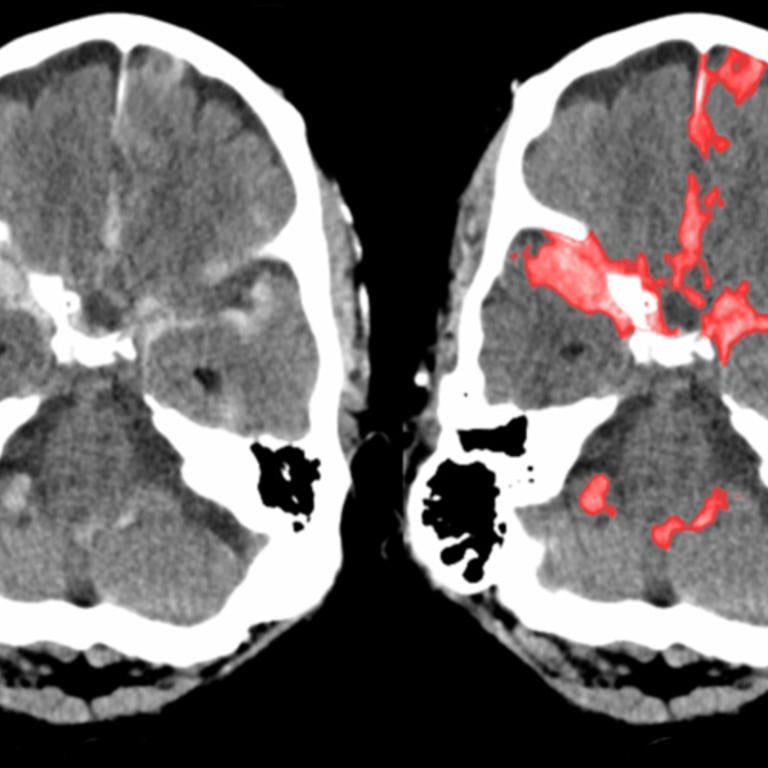

Health Care First year students developing smartphone diagnostics for Alzheimers UC Merced NIH grant to develop wireless "smart" pacemakers UC LOS ANGELES Artificial pancreas UC Irvine Vaccines for childhood diseases UC SANTA CRUZ Improving healthcare with 'smart' tech UC Davis Hydrogel to repair heart is safe to inject in humans - a first UC San Diego Shape of lung tissue fibers influences respiratory elasticity UC Riverside Engineering faster healing and better drug delivery UC Santa Barbara With AI, machines become experts at reading brain scans UC BERKELEY Advancing eye screening with machine learning UC BERKELEY Studying the brain as a network UC RIVERSIDE Student inventors receive $2M for wearable BAC monitors UC SANTA BARBARA New bioengineering master's degree bridges engineering and medicine UC SAN DIEGO Publication on TMJ advancements UC IRVINE The hygiene hypothesis UC SANTA CRUZ New frontiers in gene editing UC BERKELEY Student app translates medical jargon for non-English speakers UC MERCED Illuminating the dark matter UC SANTA BARBARA Window to the brain UC RIVERSIDE Making lead pipes safe UC BERKELEY New computational tool to pinpoint origins of bacteria on humans UC LOS ANGELES Engineering proteins for better drug delivery UC MERCED Making high energy light to fight cancer UC RIVERSIDE Diversifying the human genome for cancer research UC SANTA CRUZ Brain-computer interface to treat neurological conditions UC LOS ANGELES Engineering human-like nerve tissue UC RIVERSIDE